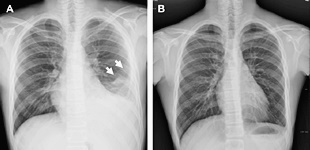

흉부X선 검사와 늑막 생검으로 진단이 가능해요. 청진시 호흡음이 감소되거나 가슴을 두드렸을 때 둔탁한 느낌이 들기도 합니다. 진단에 명확하지 않은 경우 흉강내시경을 이용하기도 해요.

흉통과 염증을 개선하기 위해서 비스테로이드 소염제가 처방될 수 있는데요. 폐렴이 원인인 경우에는 항생제를 사용합니다. 화학요법 후 증상이 호전되지 않으면 경우에 따라 수술이 필요하기도 합니다.